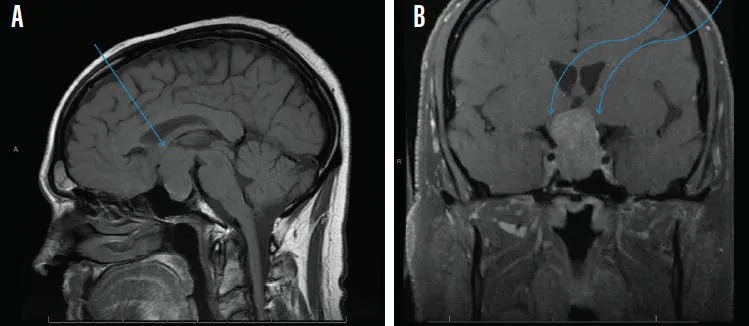

⭐ A pituitary adenoma compressing the optic chiasm is a classic cause of bitemporal hemianopsia.